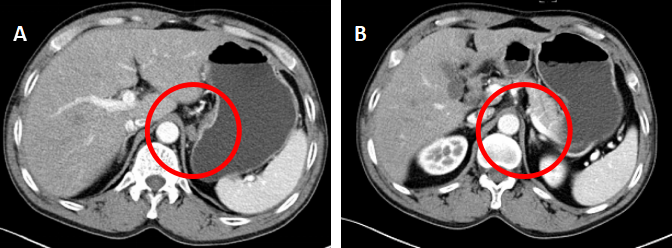

病例介绍 患者初诊信息: 蔡XX,男性,74岁。2018年5月因腹胀就诊于南昌大学第一附属医院。 MRI(2018.06.05)示:...